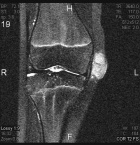

14 year old female with a tender right knee mass which has been enlarging for five months